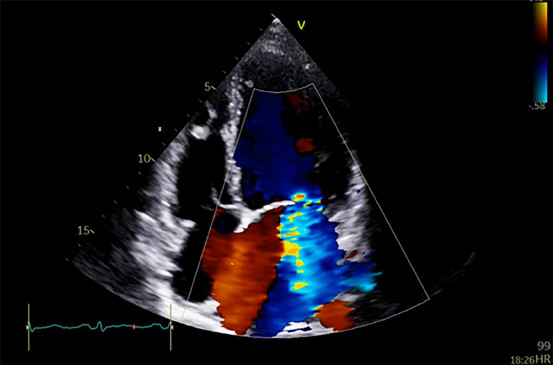

Echocardiography revealed a severely dilated and dysfunctional left ventricle (LV) with left ventricular ejection fraction (LVEF) 20%, borderline right ventricular (RV) function, and severe secondary mitral regurgitation (Figure 2).

Fig. 2

Transthoracic echocardiogram showing severe dilated left ventricle and severe secondary mitral regurgitation